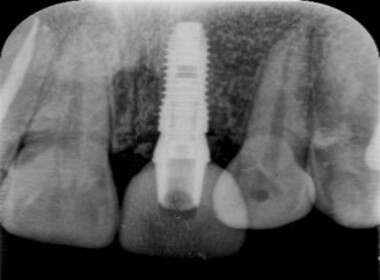

| 0114 #16 右上第一大臼齒 |

![]() |